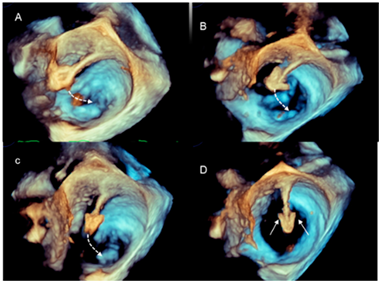

| Advancement and steering of device in the left atrium | 3D TEE allows the visualization of real-time, three-dimensional images of the motion of the GC and clip delivery system into the left atrium towards the MV. The dotted arrows in panels A–C point at the motion of the catheter. The arrows in panel D point at the arms of the clip. Of note is that the spatial relationship between the device and MV is easily understandable. |  |

| Positioning the arms perpendicular to the coaptation line | Before the advent of 3D TEE, this step was guided by 2D TEE in a transgastric short-axis view at the level of the tip of the mitral leaflets. This cross-section is often difficult to obtain. Conversely, 3D TEE provides images easily and they are immediately understandable by interventionists, who can manipulate the system while adjusting the position. Figure A–D show a still frame of the position of the clip delivery system. |  |